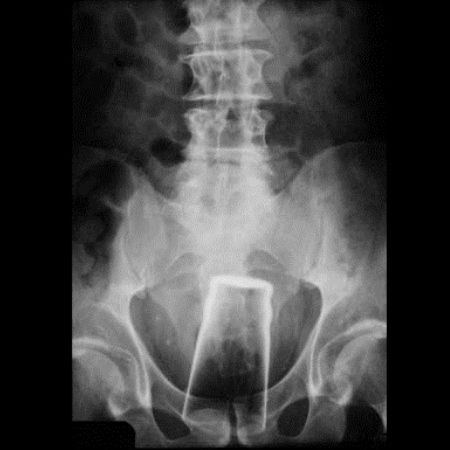

瓶は変態系統のお遊びの結果だろうな

お尻は日本でもたまーに救急に来るで

肛門に異物はよくあるらしい。やり過ぎると地主になってしまうので程ほどにね。

尻に異物が入る時はだいたい「転んだ拍子に」って言うけど医療関係者はそんな与太話は誰も信じてないだろうね。

ボトルとか瓶とかよくお尻に入れられたな